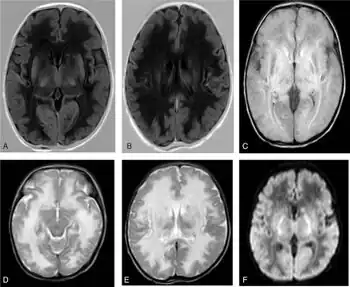

- ↑ Yamada, Kei (5 May 2021). Advances in Diffusion-Weighted Imaging, An Issue of Magnetic Resonance Imaging Clinics of North America. Elsevier Health Sciences. p. 151. ISBN 978-0-323-75997-7. Retrieved 7 July 2023.